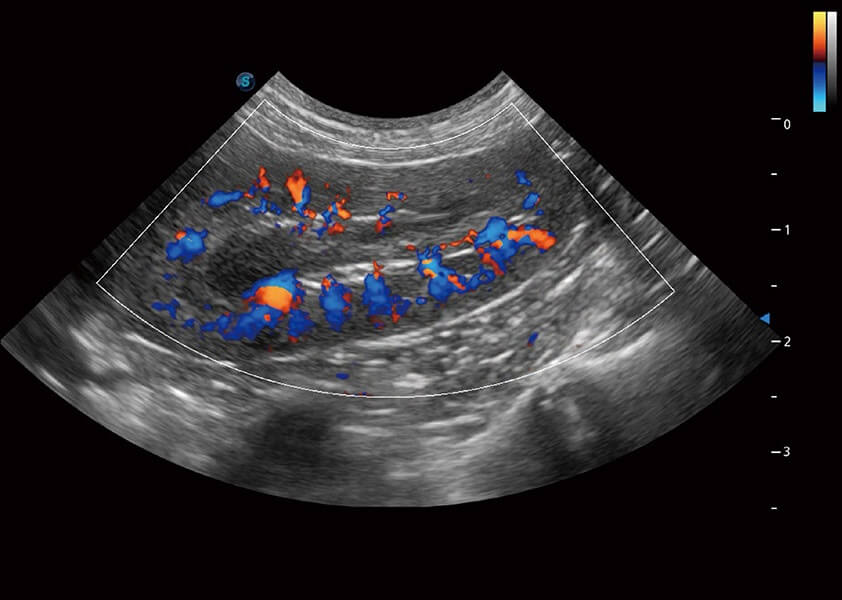

ProPet 60 作为一款高端台式动物超声设备,为动物医生的日常诊断提供了一系列贴合动物临床需求、解决临床实际问题的高级成像功能。凭借全系列高清探头,满足医生对腹部、心脏、生殖、浅表、肌骨等成像的所有需求,切实帮助您提升检查效率,提高诊断信心。

动物是人类最亲密的朋友和最值得信赖的伙伴。哈哈体育官网也一直致力于探索动物专用的超声影像解决方案。 全新推出的ProPet系列,是哈哈体育官网在动物超声影像智能化、专业化、精准化的一次跨越式革新。动物不能用言语来表述自己的不适,通过超声影像,ProPet系列搭建了动物医生与不同物种沟通的“桥梁”,为动物医生注入了“治愈之力”。